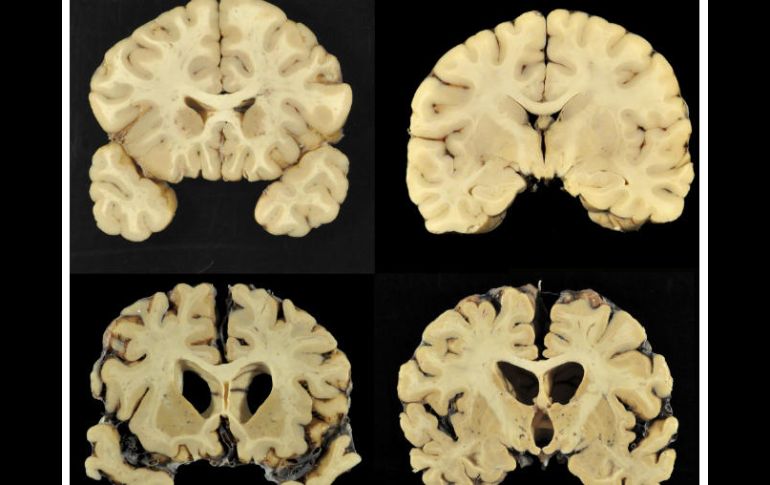

De los cerebros estudiados, 44 son de linieros, 20 corredores, 17 defensivos, 13 linebackers, siete quarterbacks y un pateador. AP / ESPECIAL

CIUDAD DE MÉXICO (25/JUL/2017).- En un estudio que realizo la neuropatóloga Ann Mckee a cerebros de ex jugadores de la NFL fallecidos, habría encontrado que en 110 de las 111 muestras existía encefalopatía traumática crónica, o CTE, la enfermedad degenerativa que se cree es causada por golpes repetidos a la cabeza.

De los 110 cerebros diagnosticados con CTE, 44 corresponden a personas que se desempeñaron como linieros, 20 corredores, 17 defensivos profundos, 13 linebackers, siete quarterbacks e incluso un pateador.

El CTE tiene como síntomas mareos, incluyendo pérdida de memoria, confusión, depresión y demencia. Los problemas pueden surgir años después del último golpe recibido.